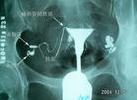

輸精管堵塞可以造成堵塞性無精子症,臨床上也稱之為假性無精子症,其臨床表現及特點是:睪丸大小正常,無精子,血清促卵泡生成素(FSH)及睪酮含量正常,睪丸活組織病理檢查結果正常。但要確診輸精管堵塞,則必須進行造影檢查。

輸精管道堵塞。檢查輸精管堵塞的方法可根據具體醫療條件來確定。最簡單易行的方法的睪丸組織活檢,即檢查睪丸活組織。 如果血中促卵泡素和睪酮含量正常,睪丸活組織檢查也正常,可以肯定是輸精管道被堵塞了,或者是先天性輸精管發育不全。否則,可能是生精功能問題。也可以做一次X光照相,即做一次輸精管精囊腺造影術。